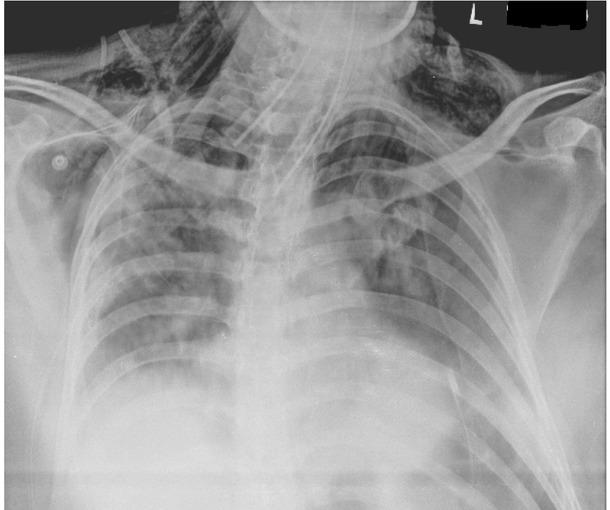

The hospital cardiothoracic team were requested to insert 30 French sized intercostal drains on both sides in the 4th intercostal space. After their insertion the drains were kept under a water seal of 2 cm, and a successful respiratory wean planned to be performed within one week. (Fig. 2 A, B)

Chest xray showing extensive subcutaneous emphysema under both shoulders and pneumomediastinum.